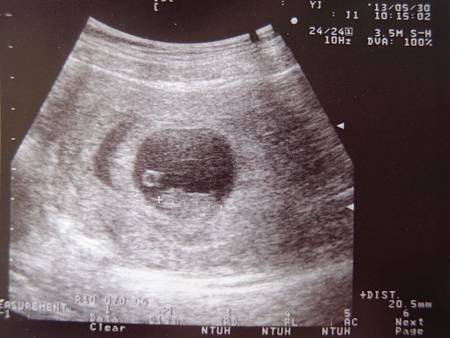

5月30日 星期四 90 36.9 45.0 17.6 早上呼吸困難喘不過氣來,雖然已經躺著休息仍舊沒有好轉所以到國泰婦產科就診,醫生表示這些都是正常現象,盡量多休息,超音波照出來有之前出血時的胎盤剝離現象,醫生說身體應該會自己吸收,只要以後出血不是鮮紅色的就OK,中午照常去上班,很累

5月24日 星期五 82 36.8 44.6 17.4 一早就有排便是軟便,早上十點多才喝安胎藥,晚上看診北鼻著床正常,可以看到橢圓形的身體形狀囉!身長1.49公分,與懷孕週數符合,老公亂講說還對我們笑喔!哈哈~~一個月後再複診檢查頸部透明帶與鼻骨確認是否有唐氏症可能性,到時可順便抽血檢查是否有漸凍人遺傳基因,如當天發展正常即發給媽媽手冊